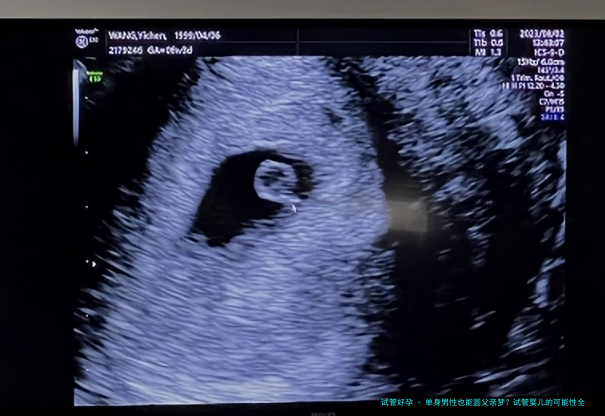

技术可行性:科学如何助力单身爸爸

技术上,试管婴儿对单身男性来说完全可行吗?答案是肯定的。近五年来,辅助生殖技术突飞猛进,比如精子冷冻、体外受精(IVF)和代孕技术已经非常成熟。根据世界卫生组织2022年的报告,全球试管婴儿成功率在过去五年平均提升了10%以上,尤其对于男性不育问题,技术解决方案更加多样化。单身男性可以通过捐试管子和代孕母亲的方式实现生育,但这需要高昂的费用和严格的医疗流程。举个例子,我有个朋友在美国通过代孕成功当上了爸爸,整个过程花了近两年时间,但他觉得一切都值得。不过,技术不是万能的,它涉及到健康风险和伦理问题,比如代孕可能引发的法律纠纷。我个人觉得,技术给了我们更多选择,但也要理性看待,不能忽视潜在挑战。